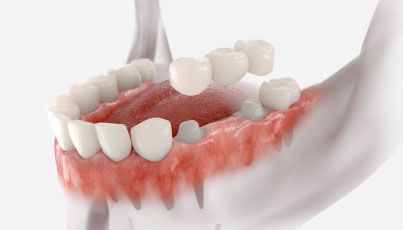

インプラント=人工の歯と考えている患者さんが多いですが、実際には歯肉に埋め込む人工的な歯根の部分をインプラントと呼びます。インプラントを埋め込んだ上からアバットメント(土台)を取り付け、最終的に人工歯を装着することで歯の見た目と機能を取り戻すことができ、その有用性から「第二の永久歯」とも呼ばれています。インプラントは新しい歯を支えるための最も重要なパーツなのです。

従来の治療法としてはブリッジや入れ歯が一般的でしたが、これらには噛み心地や見た目に関する問題があり、健康な歯を削らなければならないというデメリットがありました。

そこでインプラント治療ならば見た目を損なわず、ご自身の歯のようにしっかり噛むことができ、健康な歯を削る必要がないというメリットがあります。

ブリッジ

デメリット

• 天然歯を削る必要があり、支えとなる隣接歯への負担が大きい

• 汚れが蓄積しやすくむし歯リスクがある

• 残存歯数によっては適応不可